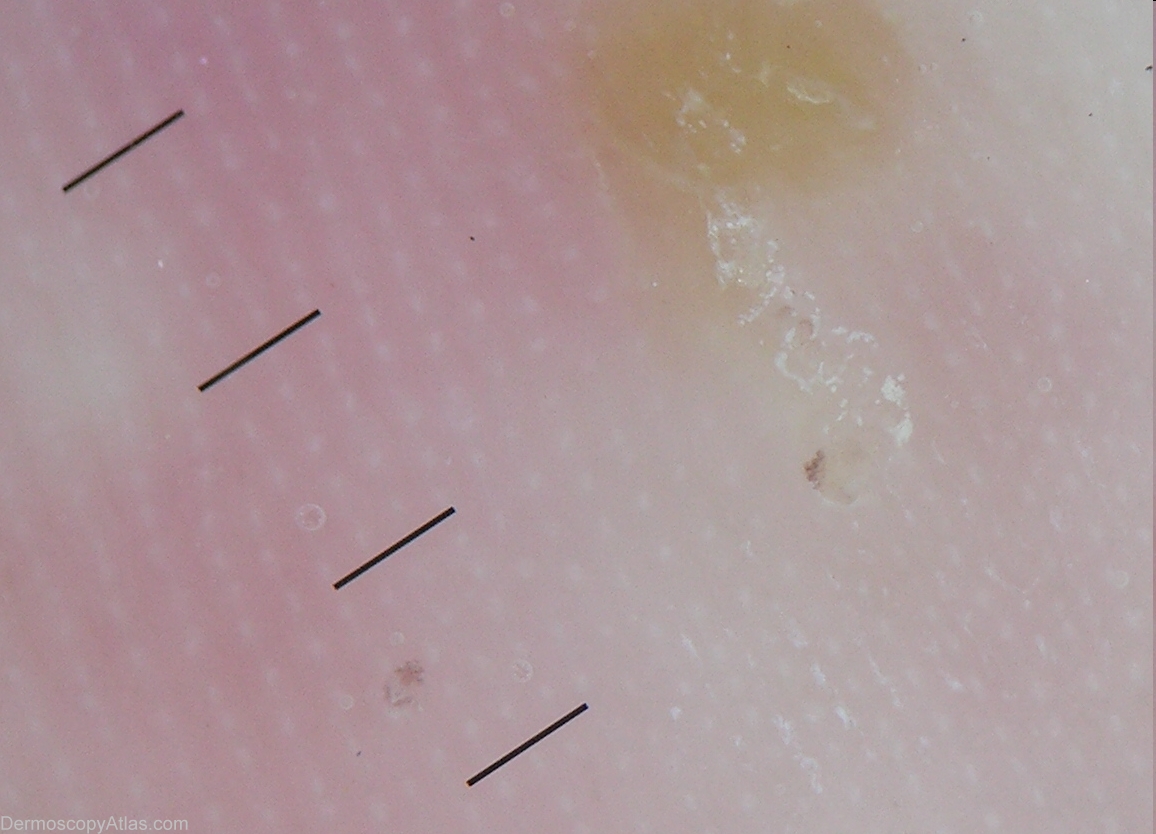

Image Number #2193 (Scabies)

Site: Foot,sole

Diagnosis: Scabies

Description: This 8 weeks old infant came for an eruption of the soles: it was made up of vesicles and pustules.

History: This infant developed a few weeks after birth this pustular eruption of the soles of the feet. Her mother and two of her brothers complained of itch. Scabies was suspected, and dermoscopy provided the proof.